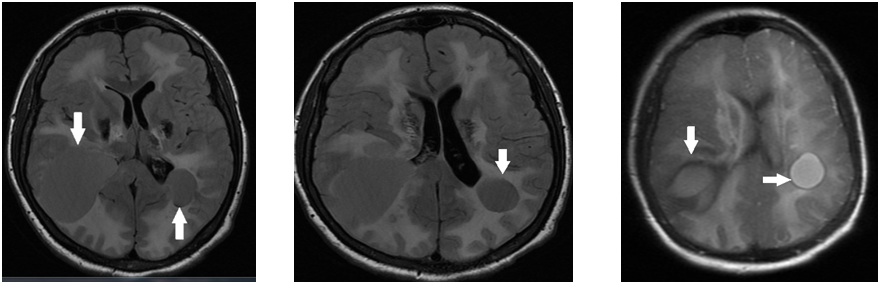

MRI Brain axial T2w images showed multiple subcortical cysts in the bilateral temporoparietal regions and diffuse hyperintense white matter changes (Figure 1).

Figure 1 MRI Brain axial T2w images showed multiple subcortical cysts in the bilateral temporoparietal regions and diffuse hyperintense white matter changes.